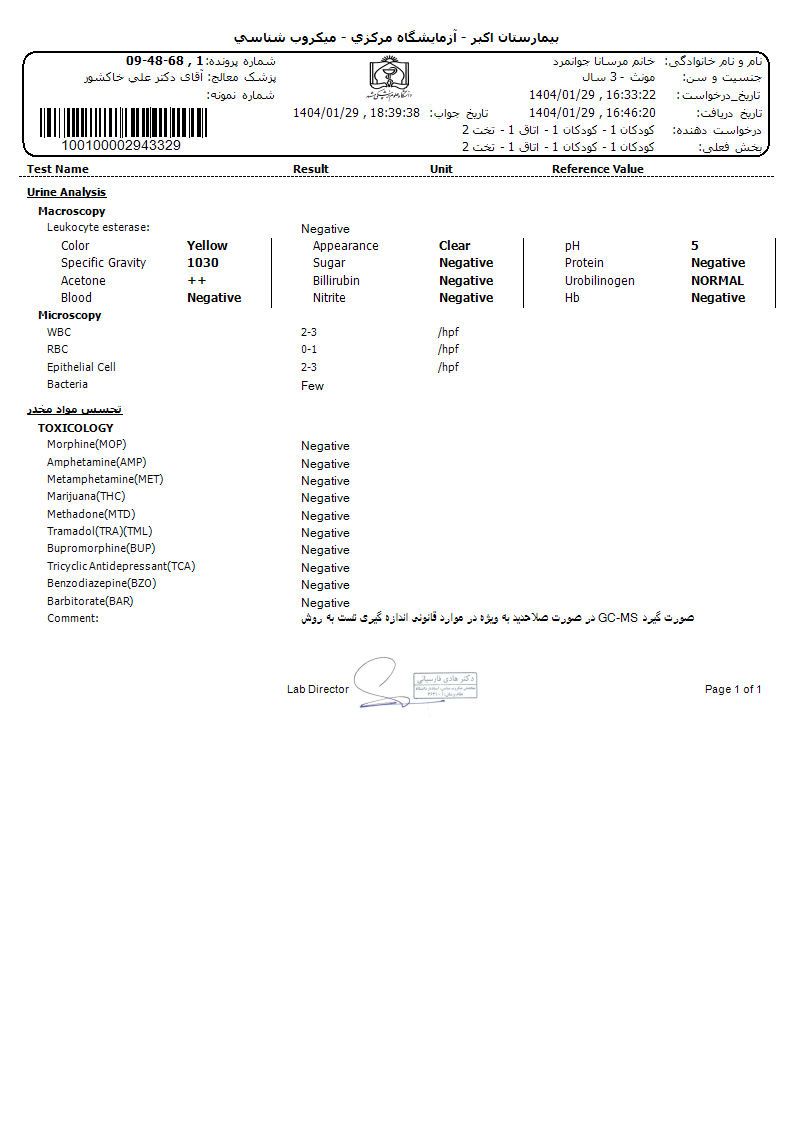

برای این کیس هنوز آزمایشی ثبت نشده است.